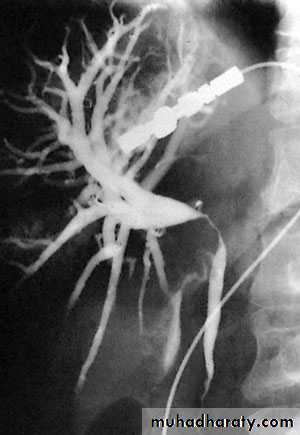

NORMAL ERCP